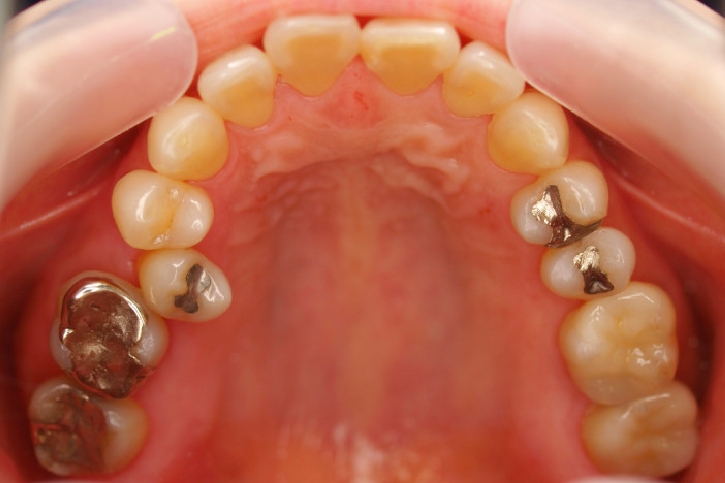

ゴールド修復

担当歯科医師:丸林浩太郎

2013年2月5日千葉市中央区 T.S様 左右6番ゴールドインレー・クラウン修復